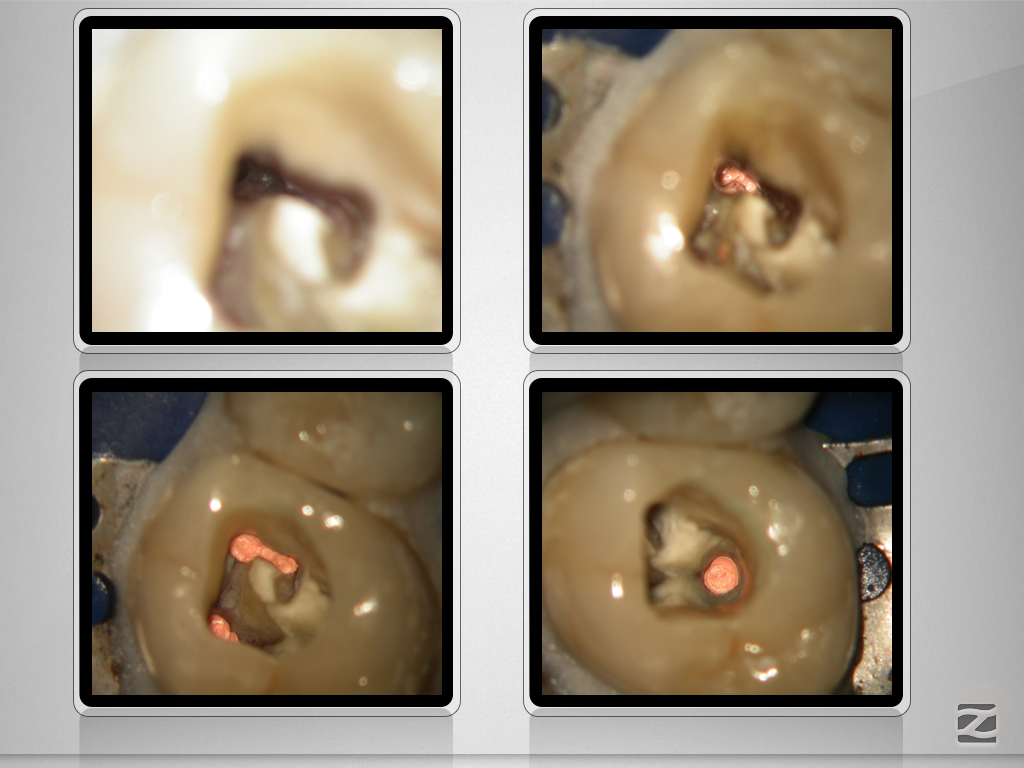

26D.013

X-Bein